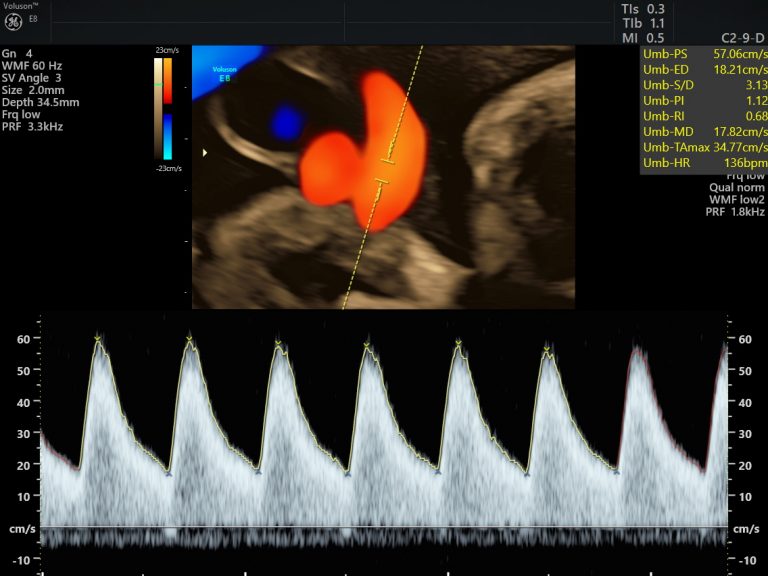

Small for gestational age babies are identified by obstetricians and referred to us for Growth and Doppler studies. This means we evaluated the adequacy of blood flow between the mom and placenta, baby and placenta as well as the flow into the baby’s brain. This information helps to plan the surveillance and delivery plan for the smaller baby meticulously. One always need to measure up the risk of being small intra-uterine, versus the risk of neonatal complications due to preterm delivery.